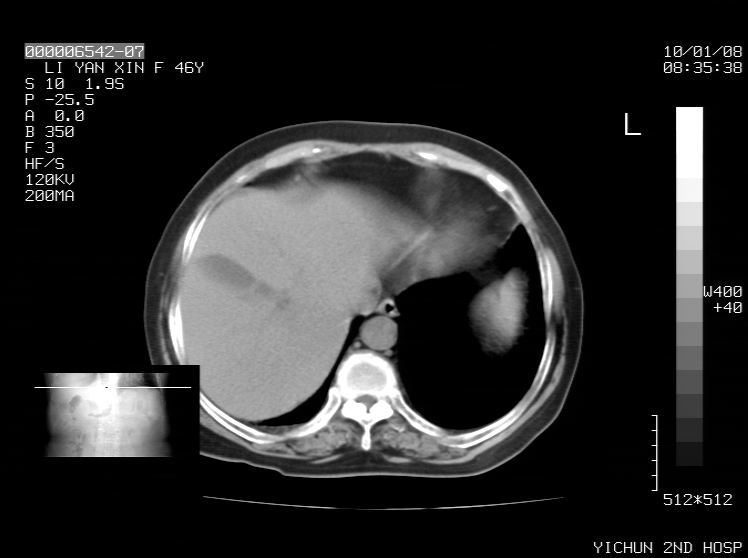

右侧膈膨升,胆囊壁厚,右侧肾脏缺如。病史?

右侧膈膨升,右肾脏切除术后

胆囊正常 肝脏正常变异

右侧膈膨升,肝内钙化灶,胆囊壁厚,右侧肾脏缺如。病史?

右膈膨出,肝脏变异,肝内钙化,右肾缺如,脾大。

右侧膈膨升,肝内胆管结石?

肝脏变异致膈升高,肝左叶肝内胆管结石.右肾萎缩,左肾代偿肥大.

右侧膈膨升,肝内钙化灶,胆囊壁厚,右肾萎缩或发育不良。